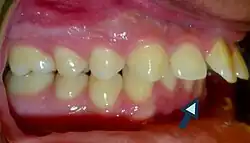

• Patients with increased overjet or lip incompetence are also at a higher risk of suffering traumatic injuries in the upper incisors (Schatz et al., 2020).

Overjet